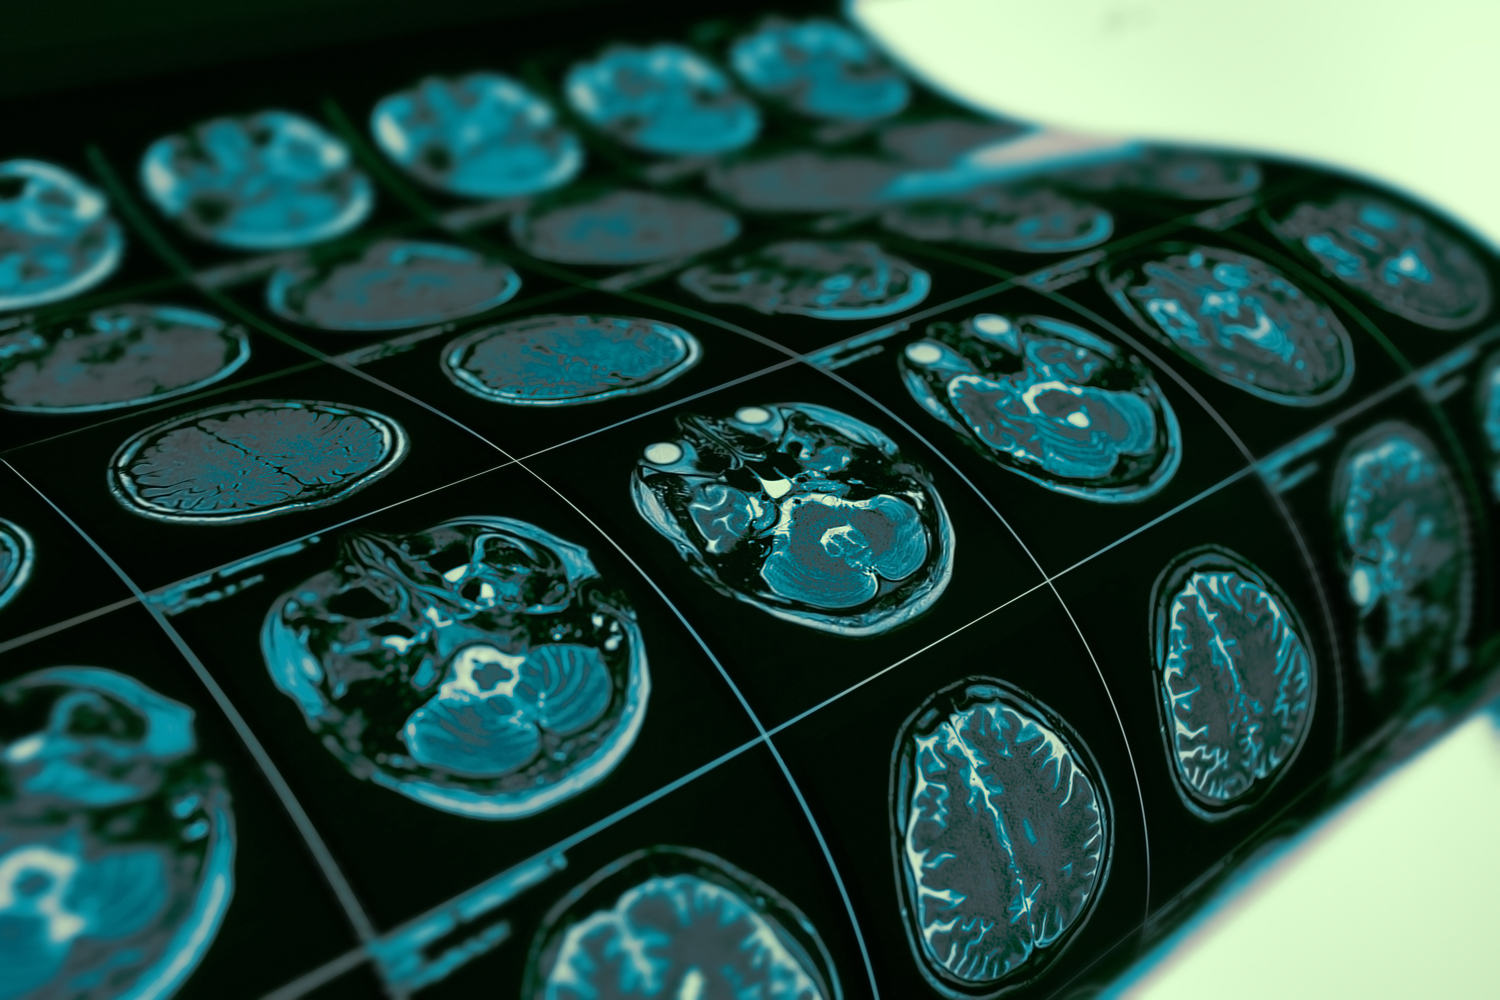

Once believed to be a rare form of dementia, the prevalence of advanced neuroimaging technology such as computed tomography (CT) and magnetic resonance imaging (MRI) has shown that subcortical vascular dementia might in fact be the most common form of vascular dementia. Caused by widespread, microscopic areas of damage to the brain from the thickening and narrowing of arteries that supply blood to the subcortical areas of the brain, the progression of this type of vascular dementia can be similar to Alzheimer’s, which sees a gradual degradation of cognitive ability.